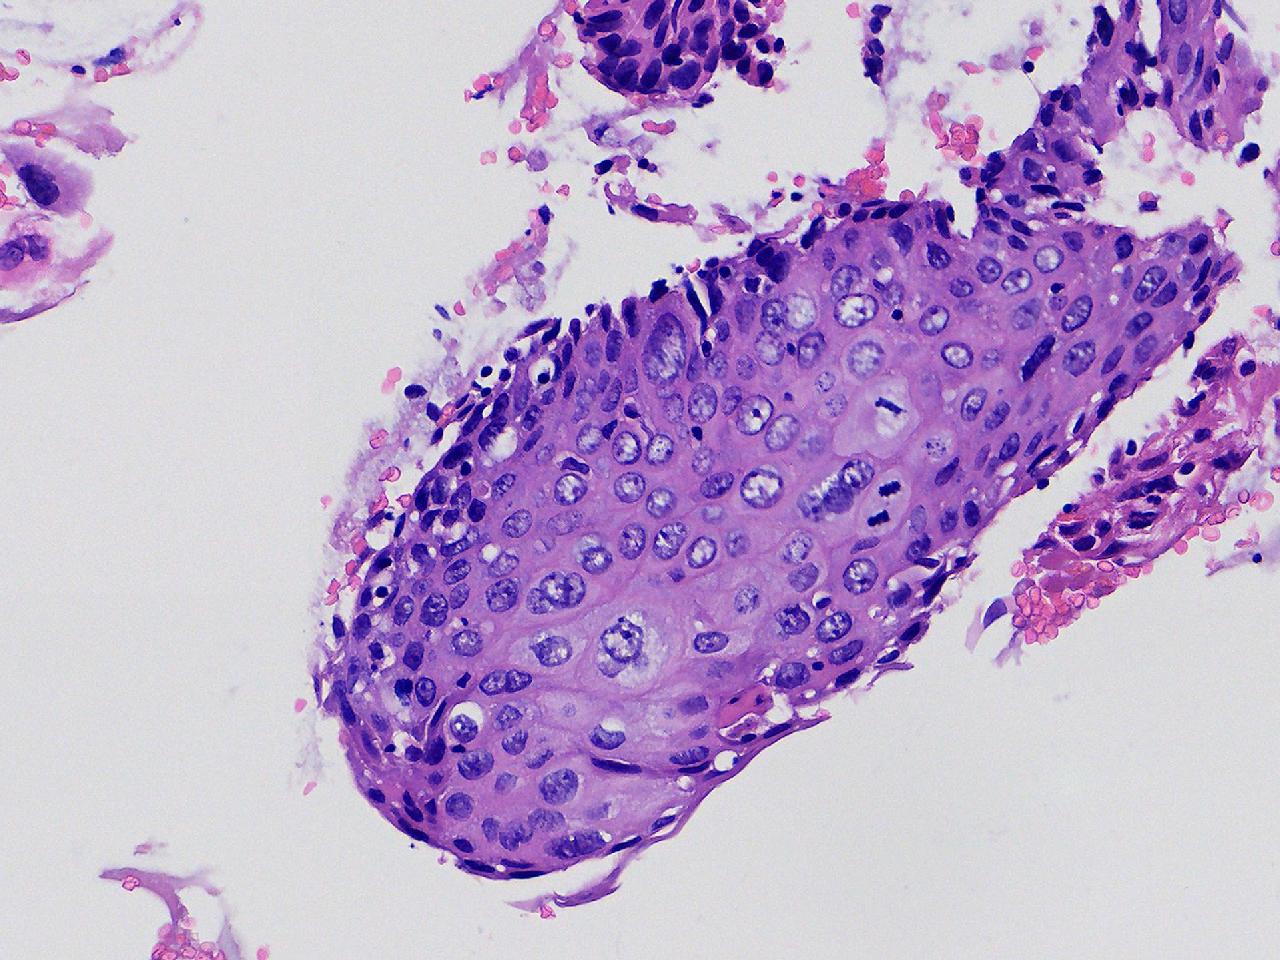

CIN1级? CIN2级?

女,48岁,宫颈3.5.6点活检。HPV52,58(+)。

宫颈多点活检。

灰白色不整形软组织多块。

CIN2

高级别